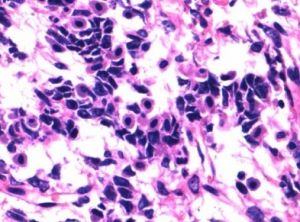

2.顯微鏡下檢查腫瘤含有支持細胞、間質細胞以及結構清楚的含Call-Exner小體的顆粒細胞、泡膜細胞。這些性索間質成分在腫瘤中相互混雜,而不是相互獨立的成分。

含有支持細胞、間質細胞以及結構清楚的含Call-Exner小體的顆粒細胞、泡膜細胞,並在腫瘤中相互混雜。